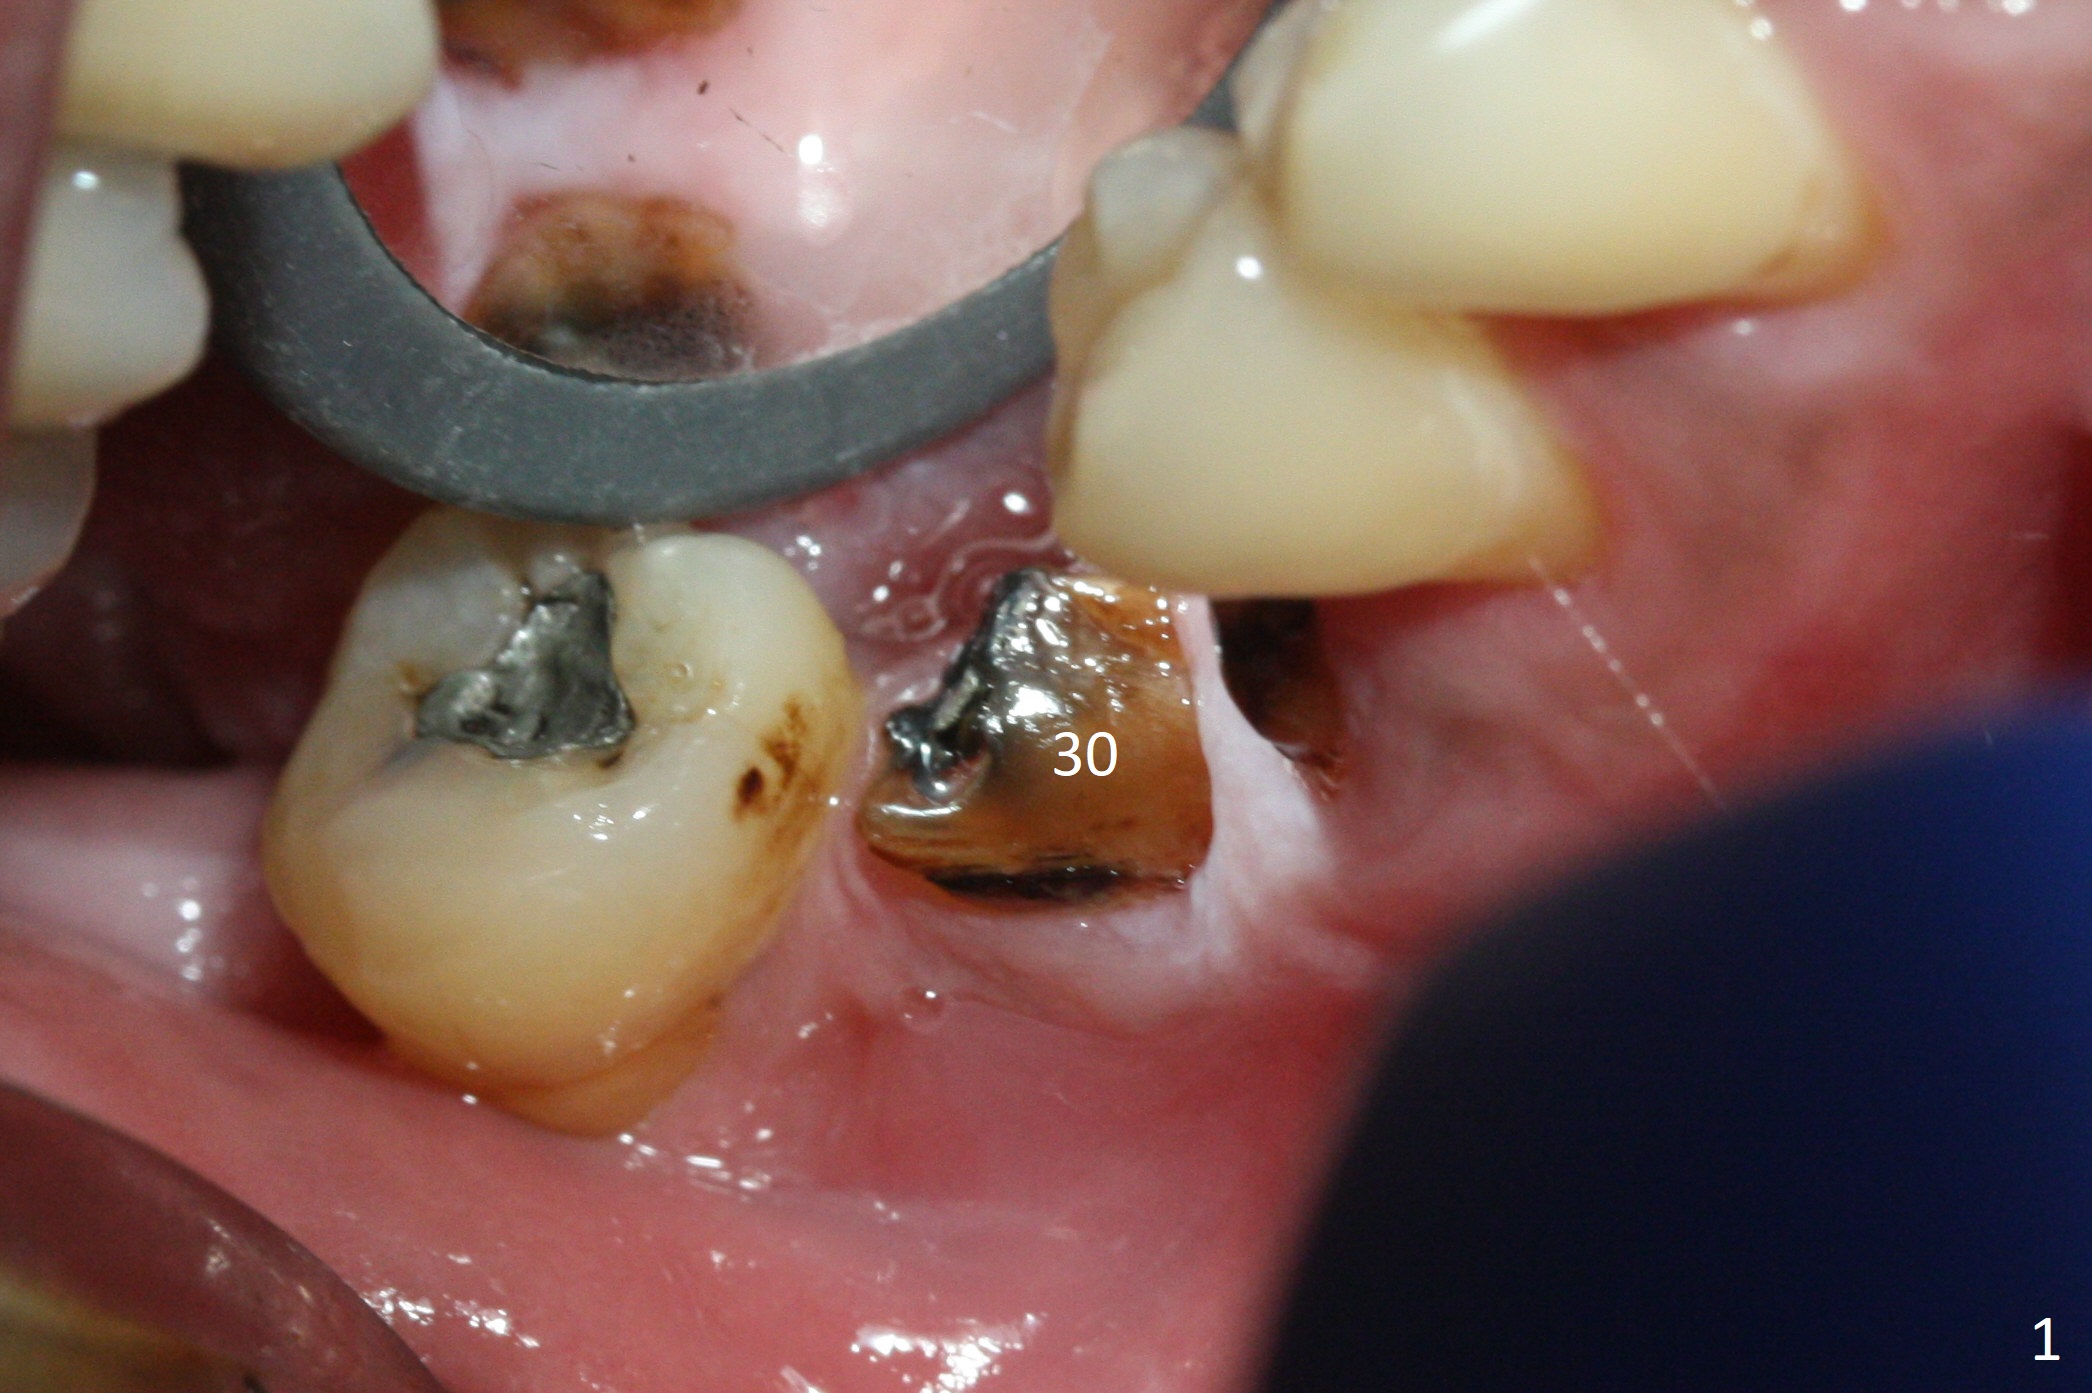

When the residual roots of the tooth #30 (Fig.1) are removed, the buccal crest is found ~ 2 mm apical to the lingual one (Fig.2 <); while the initial depth of osteotomy is 11.5 mm (yellow lines), the parallel pin is 10 mm long. To place a 5x11.5 mm implant at the level of the buccal crest (Fig.4 (>45 Ncm)), subsequent osteotomy depth is 13 mm using the lingual crest as a landmark (Fig.3 (4 mm drill in place)). After insertion of a 5.7x5.5(3) mm abutment, Vanilla Graft is placed (Fig.5 * with 2 mm buccal gap). The abutment with a provisional is loose 4 months postop (Fig.6). The permanent restoration is cemented 6 months postop. The abutment screw is loose and fractured 8 and 11 months post cementation, respectively (Fig.7). The fractured screw seems to be loose within the implant well and is easily re-winded out using Screw Removal Kit (sr-kit.html). When the crown/abutment at #30 is loose 2nd time 1 year 7 months post cementation (Fig.8 taken post retightening), the screw at #19 fractures. The tooth #2 needs a crown. The patient cannot use the anterior teeth, since the teeth #8 and 9 have root fracture. Can extraction and bone graft increase bone height? The screw re-fractures 9 months later (Fig.9). The dislodged crown is sectioned; the abutment is reseated completely (Fig.10) for a new crown. The tooth #2 needs RCT, B-U and crown, while the tooth #1 extraction (Fig.11).